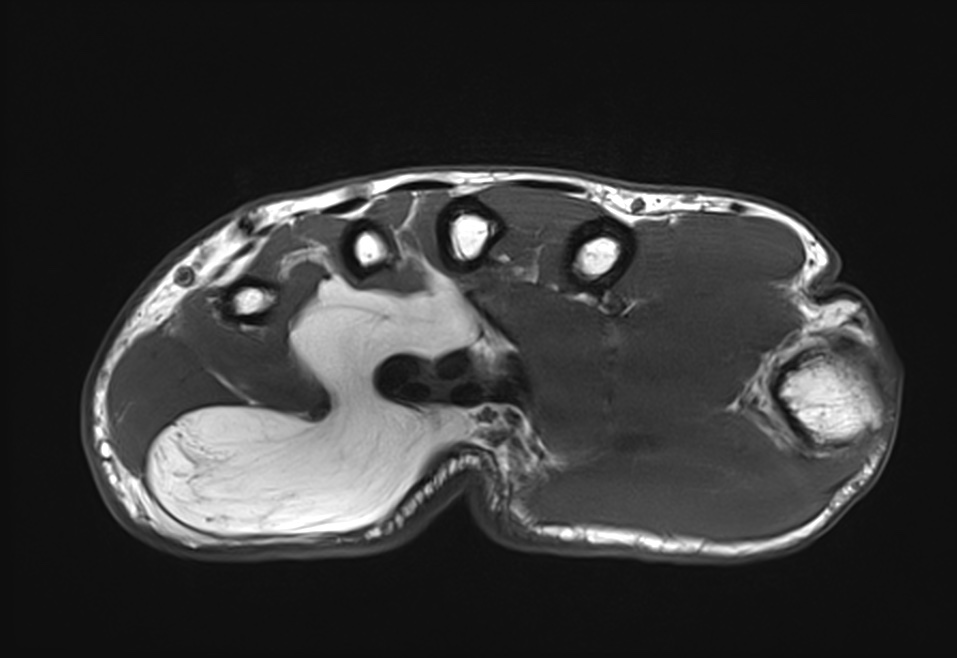

On distingue différents types de tuméfaction de la main outre le kyste synovial en fonction des tissus atteints:

- les tumeurs osseuses (chondrome, exostose…)

- les tumeurs des parties molles (tumeur à cellules géantes, lipome, tumeur glomique, tumeurs vasculaires…)